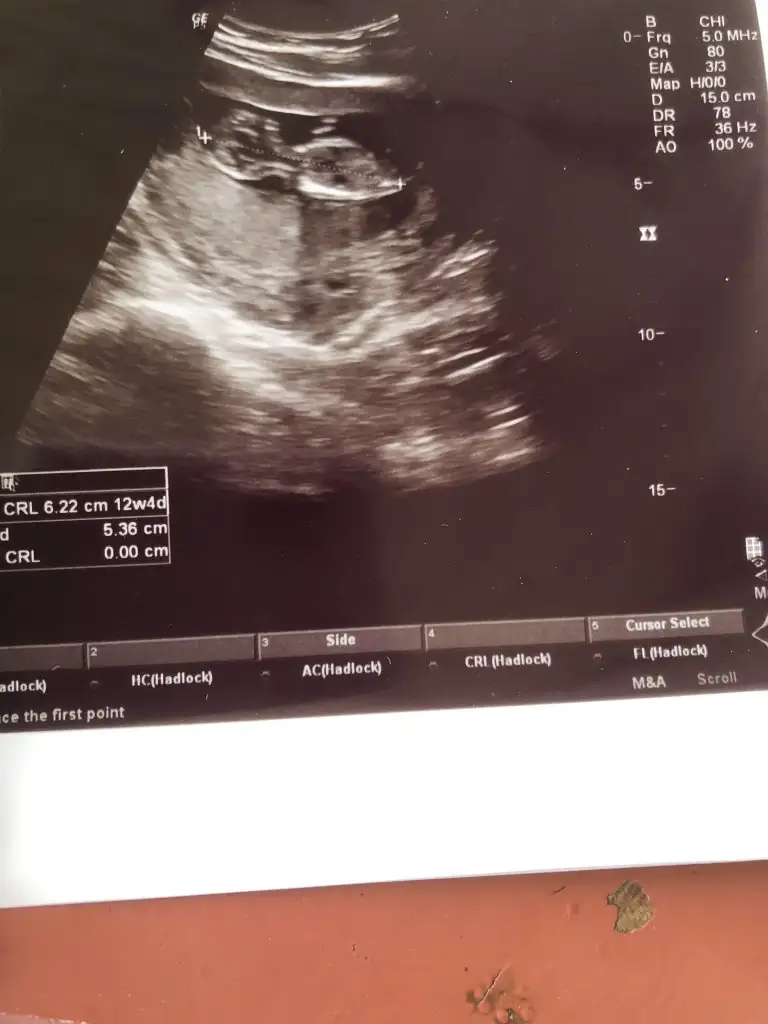

kuzum buna tahminde bulunamadım, 6 haftalıkkrb yolk kesen görünüyor zaten diğerinde de bebek üstü yazılarla kapalıCanım benim de 6 haftalıkken bu ultrasonum yorum yapabilir misin diğeri 8 haftalıktı

11+4 ama ultrasonda 12+4 cıktı karından bizede tahmin yürütürmüsünüz